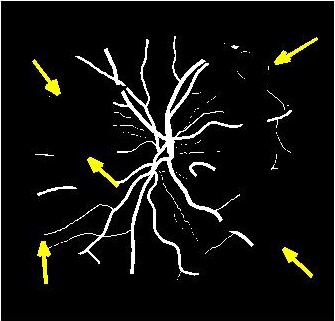

Figure 4 (a) shows an example retinal image followed by its ground truth manual segmentation in Figure 4 (b). Figure 4 (c) shows segmentation result for scaling factor when using the original HR images to train the U-Net followed by the results when trained on the super resolved images generated by , (Figure 4 (d)), (Figure 4 (e)), (Figure 4 (f)), SR-RF (Figure 4 (g)), SSR (Figure 4 (h)) and (Figure 4 (i)). Obviously the results from provide results most similar to those of HR images. This is also validated by the quantitative results in Table 3. The areas where different methods are unable to obtain accurate segmentation are highlighted by yellow arrows. Due to poor quality of super resolved images most of the methods do not segment the finer vasculature structures, while SSR and SR-RF are unable to segment some of the major arteries. Importantly, our method performs much better than the low resolution image () which performs poorly due to low resolution.

![]() |

| (a) | (b) | (c) | (d) | (e) |

| (f) | (g) | (h) | (i) | (j) |